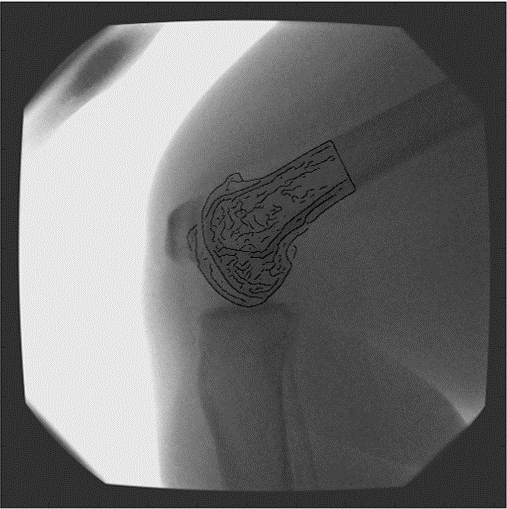

The OrthoVis software is now an intrinsic part of a major clinical trial to evaluate the performance of three different artificial knee designs. The software package has been used to measure the knee motion data for over 170 patients and, when completed, the data collected from the trial will form the largest ever study of knee motion.

- Saadat S., Perriman D., Scarvell J. M., Smith P. N., Galvin C. R., Lynch J. & Pickering M. R. (2022), An efficient hybrid method for 3D to 2D medical image registration, International Journal of Computer Assisted Radiology and Surgery, Vol. 17, pp. 1313 – 1320, doi: 10.1007/s11548-022-02624-0.

- Saadat S., Asikuzzaman M., Pickering M. R., Perriman D. M., Scarvell J. M. & Smith P. N. (2021) A Fast and Robust Framework for 3D/2D Model to Multi-Frame Fluoroscopy Registration, IEEE Access, Vol. 9, pp. 134223 – 134239, doi: 10.1109/ACCESS.2021.3114366.

- Lynch J. T., Perriman D.M., Scarvell J.M., Pickering M. R., Galvin C. R., Neeman T. & Smith P. N. (2021) The influence of total knee arthroplasty design on kneeling kinematics: A prospective randomized clinical trial, Bone and Joint Journal, Vol. 103, pp. 105 – 112, 10.1302/0301-620X.103B1.BJJ-2020-0958.R1.

- Ward T. R., Hussain M. M., Pickering M. R., Perriman D., Burns A., Scarvell J. & Smith P. N. (2021) Validation of a method to measure three-dimensional hip joint kinematics in subjects with femoroacetabular impingement, HIP International, Vol. 31, pp. 133 – 139, doi: 10.1177/1120700019883548.

- Lynch J. T., Perriman D. M., Scarvell J. M., Pickering M. R., Warmenhoven J., Galvin C. R., Neeman T., Besier T. F. & Smith P. N. (2020) Shape is only a weak predictor of deep knee flexion kinematics in healthy and osteoarthritic knees, Journal of Orthopaedic Research, Vol. 38, pp. 2250 – 2261, doi: 10.1002/jor.24622.

- Galvin, C. R., Perriman, D., Scarvell, J. M., Lynch, J. T., Pickering, M. R., Smith, P. N., & Newman, P. (2019). Age has a minimal effect on knee kinematics: a cross-sectional 3D/2D image-registration study of kneeling. The Knee, accepted 20 July.

- Scarvell, J. M., Hribar, N., Galvin, C. R., Pickering, M. R., Perriman, D. M., Lynch, J. T., & Smith, P. N. (2019). Analysis of kneeling by medical imaging shows the femur moves back to the posterior rim of the tibial plateau, prompting review of the concave-convex rule. Physical Therapy, 99(3), 311-318. doi:https://doi.org/10.1093/ptj/pzy144

- Akter, M., Lambert, A. J., Pickering, M. R., Scarvell, J. M., & Smith, P. N. (2014). Robust initialisation for single-plane 3D CT to 2D fluoroscopy image registration. Computer Methods in Biomechanics and Biomedical Engineering: Imaging & Visualization, Taylor & Francis, DOI: 10.1080/21681163.21682014.21897649. doi:10.1080/21681163.2014.897649

- Scarvell, J. M., Pickering, M. R., & Smith, P. N. (2009). New registration algorithm for determining 3D knee kinematics using CT and single-plane fluoroscopy with improved out-of-plane translation accuracy. Journal of Orthopaedic Research, 28(3), 334-340.